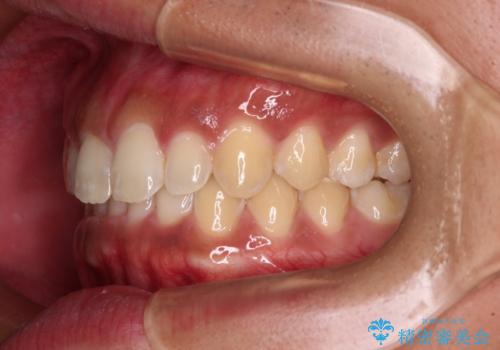

デコボコとディープバイトを治したい インビザラインによる矯正治療

- 前歯のデコボコや隙間と深い咬み合わせ(ディープバイト)を気にして来院された患者様です。

インビザラインによる上下歯列の側方拡大と後方移動、IPR(歯と歯の間を削る)にるスペースの獲得により、デコボコとディープバイトを改善することとしました。

気になっていたデコボコや隙間は改善し、きれいな歯列に整えることができました。

咬合力が非常に強い方であったため、これ以上のディープバイトの改善は困難となりました。